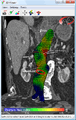

An aneurysm ruptures if the mechanical stress (tension per area) exceeds the local wall strength; consequently, peak wall stress (PWS)[27] and peak wall rupture risk (PWRR)[28] have been found to be more reliable parameters than diameter to assess AAA rupture risk. Medical software allows computing these rupture risk indices from standard clinical CT data and provides a patient-specific AAA rupture risk diagnosis.[29] This type of biomechanical approach has been shown to accurately predict the location of AAA rupture.[30]

Biomechanical AAA rupture risk prediction